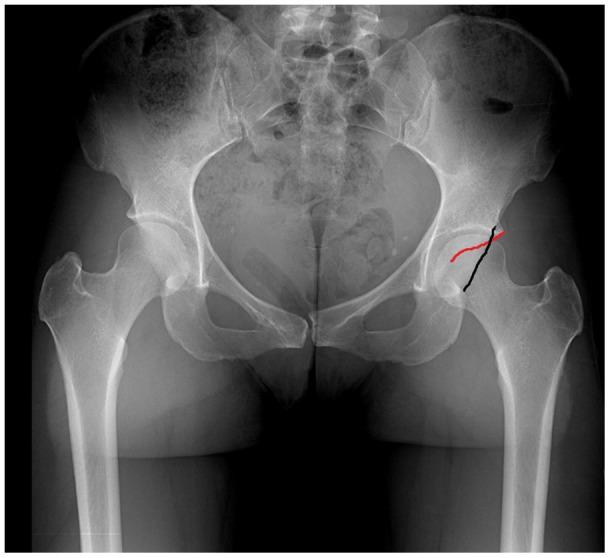

Femoroacetabular impingement (FAI) alters hip mechanics, results in hip pain, and may lead to secondary osteoarthritis (OA) in the maturing athlete. Hip impingement can be caused by osseous abnormalities in the proximal femur or acetabulum. These impingement lesions may cause altered loads within the hip joint, which result in repetitive collision damage or sheer forces to the chondral surfaces and acetabular labrum. These anatomic lesions and resultant abnormal mechanics may lead to early osteoarthritic changes.

股骨髋臼撞击症(FAI)改变髋关节力学,导致髋关节疼痛,并可能导致成熟运动员的继发性骨关节炎(OA)。髋关节撞击可由股骨近端或髋臼的骨性异常引起。这些撞击病变可能导致髋关节内负荷改变,从而导致软骨表面和髋臼盂唇的反复碰撞损伤或剪切力。这些解剖学病变和由此产生的异常力学可能导致早期骨关节炎变化。